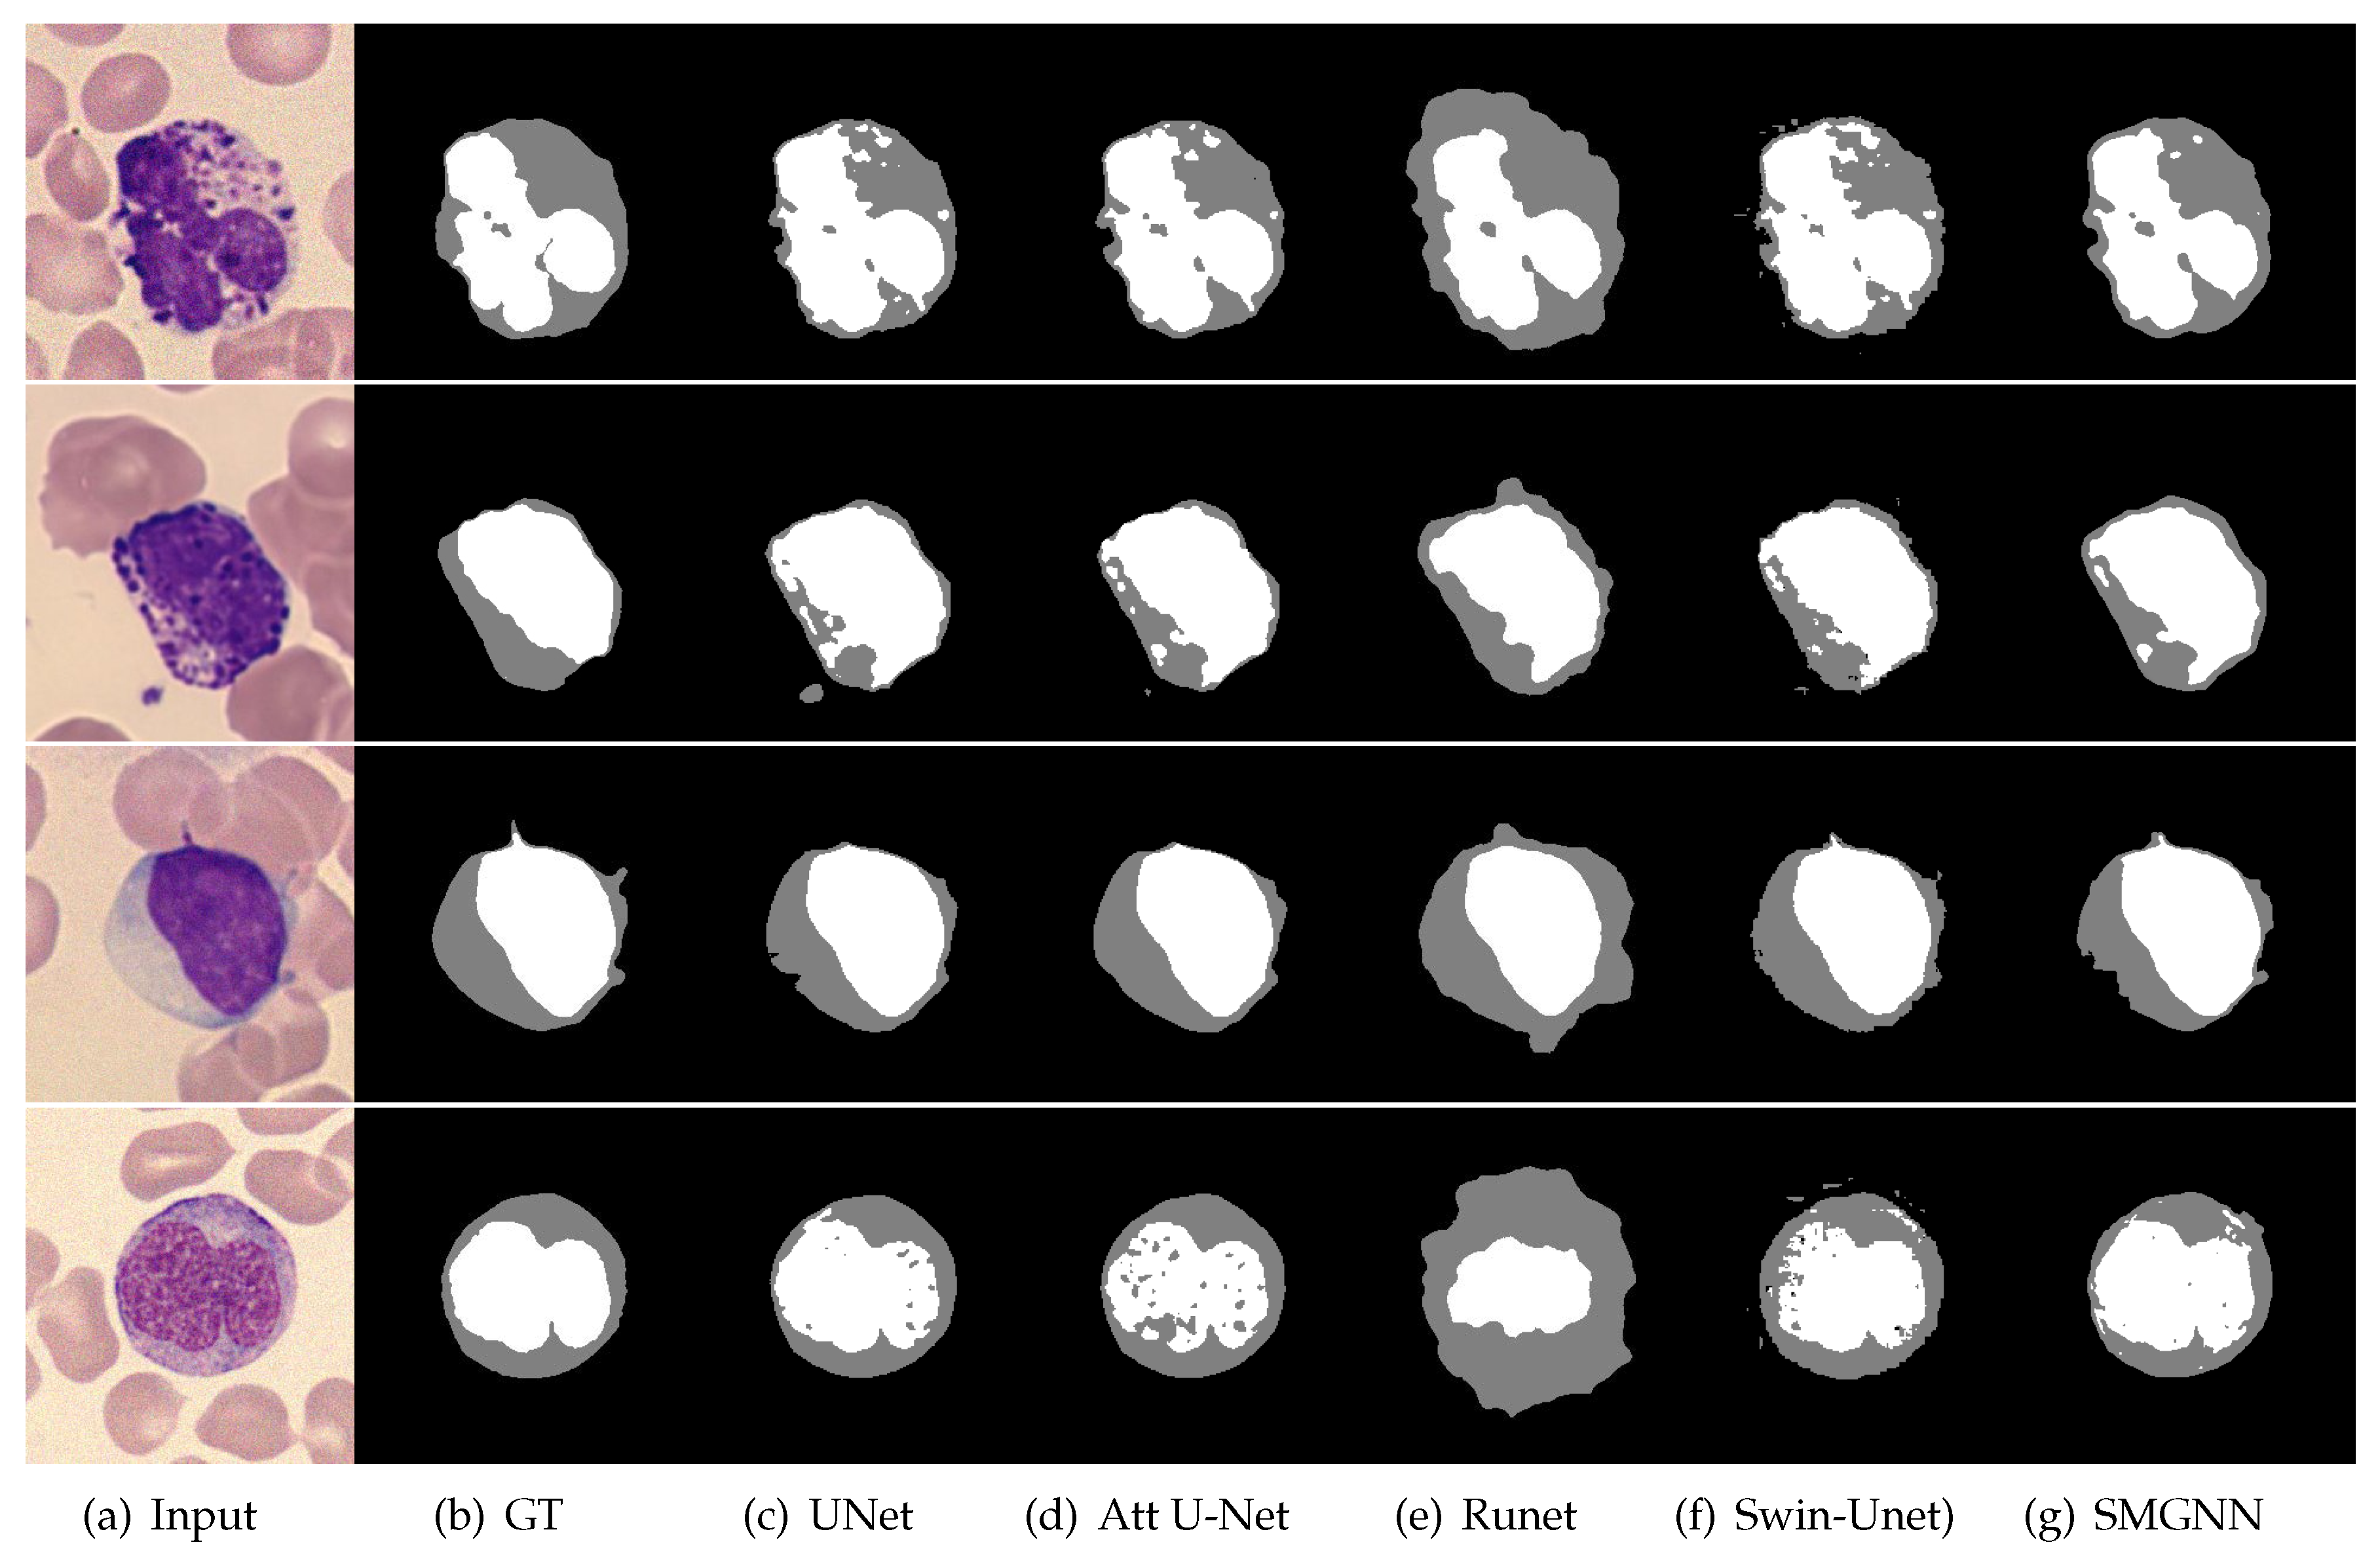

3.3. Comparison with Mainstream Deep Learning Segmentation Methods